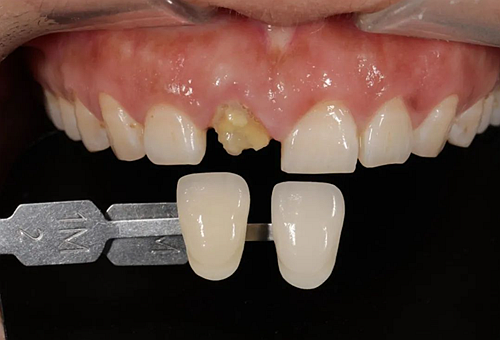

患者右上前牙因外傷冠修復(fù)體脫落來我院找口腔修復(fù)科金小婷醫(yī)師治療。經(jīng)檢查,患者剩余牙體組織少,經(jīng)溝通確認后,進行上前牙全瓷冠修復(fù)。

△術(shù)前比色